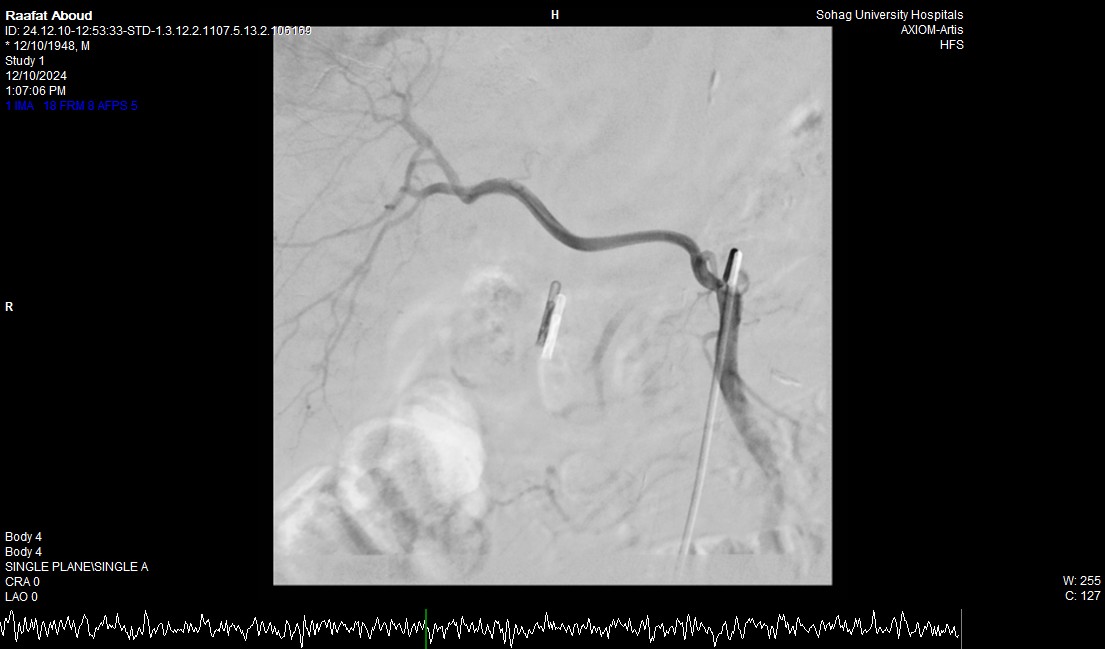

جامعة سوهاج.. أفاد الدكتور أحمد كمال، المدير التنفيذي للمستشفيات الجامعية، أن الفحوصات أظهرت وجود قرحة كبيرة في الاثني عشر وشريان نازف. نجح الفريق الطبي في التحكم بالنزيف مبدئيًا عبر تركيب مشبك معدني بالمنظار وحقن القرحة النازفة.

جامعة سوهاج.. وفي خطوة لاحقة، تم استدعاء فريق الأشعة التداخلية الذي تمكن من إغلاق الشريان النازف بشكل عاجل باستخدام جهاز القسطرة، ما ساهم في استقرار حالة المريض.

جامعة سوهاج.. أكد الدكتور محمد زاكي، رئيس قسم الأشعة، أن مثل هذه الحالات تعد من أخطر الطوارئ الطبية، حيث يتطلب التعامل معها إجراء قسطرة شريانية عاجلة لإيقاف النزيف. وأضاف أن وحدة الأشعة التداخلية مزودة بجهاز أشعة محوري متقدم مخصص لمثل هذه التدخلات، مشيرًا إلى أن هذا النجاح يعكس التعاون المثمر بين أقسام المستشفى المختلفة ووحدة الأشعة التداخلية لتقديم خدمات متميزة للمرضى.